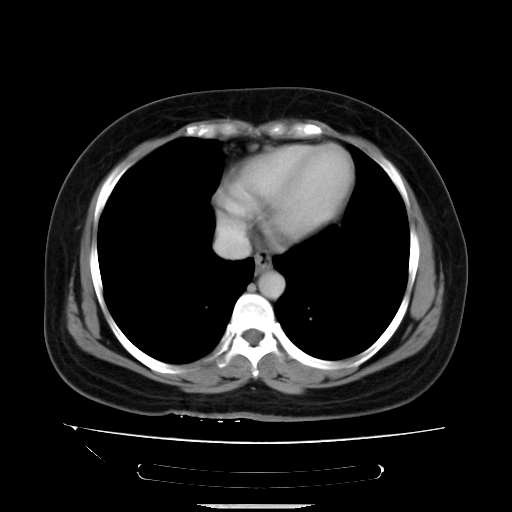

标题: CT14225:女性46岁。当地B超示肝内占位,来我院作CT检查。请 [打印本页]

标题: CT14225:女性46岁。当地B超示肝内占位,来我院作CT检查。请

支持肝癌、胆囊炎诊断。